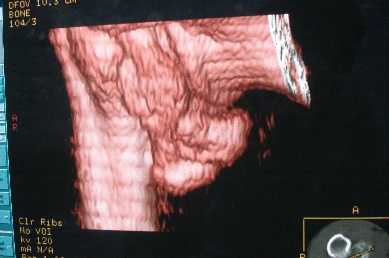

右上肢活动不便多年,最近加重。右肱骨肿瘤,请会诊!

骨软骨瘤恶变可能性大

右肱骨近断骨软骨瘤伴临近关节退变.有无恶变建议进一步检查.

右肱骨近断骨软骨瘤伴临近关节退变。

病变边缘轮廓清晰无骨质破坏,邻近软组织不肿胀,不支持肿瘤恶变。